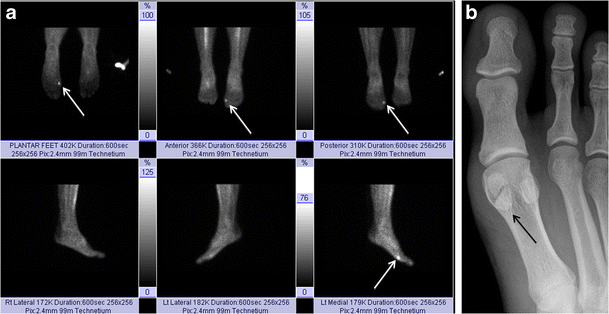

Sesamoiditis. Bone scan of the bilateral feet (a) in a patient with plantar foot pain reveals nonspecific but intense tracer uptake localising to the medial hallucal sesamoid. AP radiograph at the first toe (b) reveals a bipartite medial hallucal sesamoid with no diastasis, fragmentation or sclerosis. The patient was diagnosed with bony sesamoiditis

Chronic pain at the hallucal sesamoids may clinically be described as “sesamoiditis”, a term that encompasses the symptoms from pathology at the hallux sesamoids complex [13]. Chronic pain can be caused by stress fracture, stress reaction, osteoarthritis and osteonecrosis of the sesamoids, as well as tendinosis and capsular inflammation [27]. Repetitive and excessive axial loading in plantar flexion, such as in ballet dancing, running and even wearing high-heeled shoes, have also been postulated as risk factors for sesamoiditis [3, 27]. Excision of one sesamoid may cause abnormal biomechanical stress on the residual sesamoid [3], also increasing the risk of stress fracture and osteonecrosis.